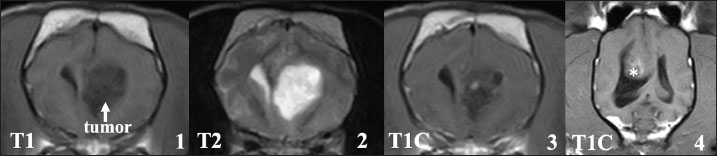

In this study, 4 cases could not complete the radiation therapy. Among these, 1 case died before starting treatment (B1), and 3 cases died during radiation therapy (B2–B4). Although the cause of death was not clearly identified because an autopsy could not be done, 2 cases that died after the first fraction showed cerebellar herniation on MRI at the first visit, possibly due to large tumor size (Fig. 5,1).

On MRI at the first admission in these 4 cases, leptomeningeal enhancement, as seen in cases A1–A4, was also observed, although the changes were less prominent (Fig. 5, 1-3). In 1 case (B2), multiple mass lesions were observed. In addition to the primary lesion, another presumed tumor tissue was observed, which appeared to be contiguous with the meninges on MRI, showing clear enhancement (Fig.5, 4-7).

Fig. 5. MRI at the first visit of the cases that died early after visiting our hospital (cases B2–B4, T1: T1-weighted image, T2: T2-weighted image, and T1C: T1-weighted image with contrast medium). Upper lane 1: Cerebellar herniation was observed on the sagittal plane (yellow arrow) in case B3, possibly due to the large tumor size. Upper lanes 2 and 3: At the time of the first visit, enhancement was already observed in the leptomeningeal region around the brainstem (B4, yellow arrow), but was less prominent compared with cases A1–A4. Lower lane 4–7: In case B2, the tumor tissue considered to be the primary lesion showed heterogeneous enhancement (4, 5). Furthermore, another mass contiguous with the meninges was observed. This mass shows a clear enhancement (6, 7, yellow arrow).